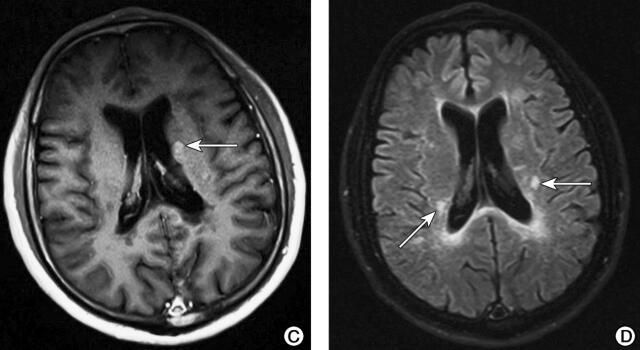

①头颅MRI(2015-12-30)(图1):双侧额叶深面、侧脑室旁、半卵圆中心白质内多发点状稍长T1稍长T2信号,FLAIR高信号,部分病变DWI高信号,增强扫描左侧基底节区、侧脑室旁见数个斑点状强化。②头颅MRI(2016-9-14)(图2):双侧基底节、侧脑室旁、半卵圆中心见多发点片状长T1长T2信号,部分与脑室垂直,DWI呈稍高信号;增强扫描未见异常强化;MRS示较大病灶处Cho峰轻度升高、NAA峰轻度下降,未见高灌注。③头颅MRI(2017-6-1):双侧基底节、侧脑室旁、半卵圆中心见多发点片状长T1长T2信号,部分与脑室垂直,DWI低信号,与2016年9月14日片比较未发现新发病灶。④颈胸椎MRI(2015-12-30)(图3):C3~C5脊髓稍长T1稍长T2信号,增强扫描呈环形强化。

图2 头颅MRI(2016-9-14)检查结果

注:A.双侧侧脑室旁、半卵圆中心见多发点片状长T2信号,部分与脑室垂直(箭头);B.右额叶DWI稍高信号(箭头);C.FLAIR像呈稍高信号(箭头);D.增强扫描未见异常强化;E.MRS显示Cho轻度升高、NAA峰轻度下降(箭头)